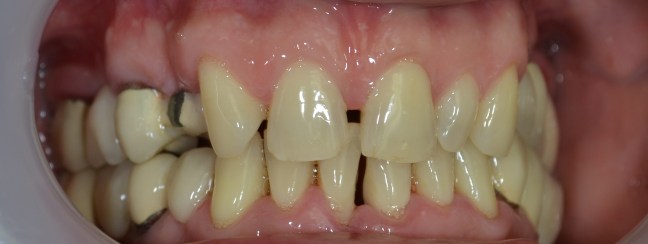

Kozmetikai és funkcionális kezelés: a kopott, elszuvasodott fogak szanálásával, hiányzó frontfogak híddal történő pótlásával, harapás megemelésével.

A választott korona típusa: CAD/CAM (komputer vezérelt tervezés/megmunkálás) technológiával készült cirkónium (fémmentes) szóló koronák, front híd.

A választott fogszín: BL 3 .

A protetikai munka elkészülésének ideje: 10 munkanap.